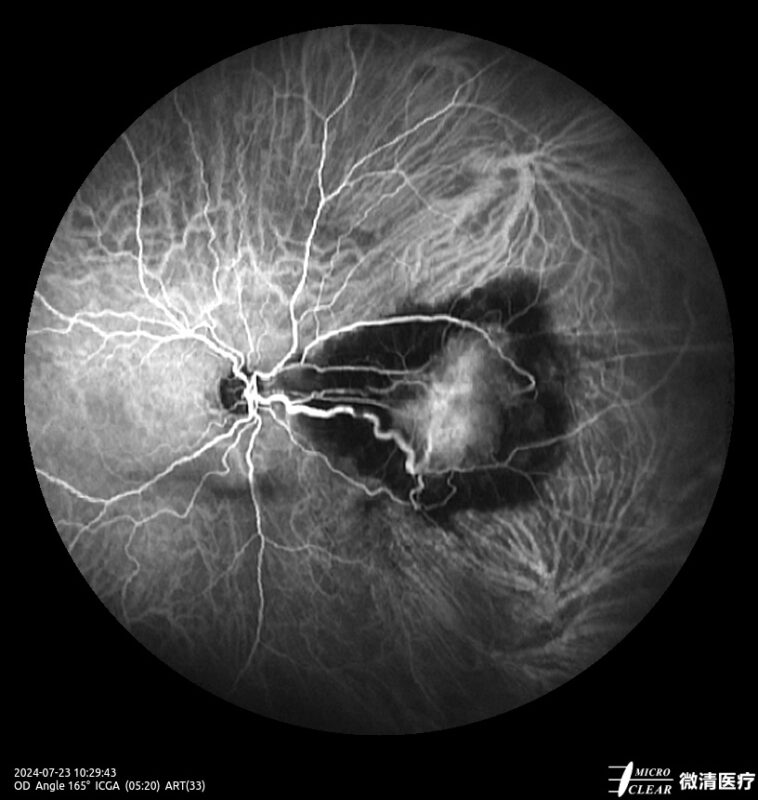

Ultra-groothoek en multimodale fundusangiografie gebaseerd op confocale scanning laser oftalmoscopie (CSLO).

- Fundusfluoresceïne-angiografie (FFA)

- 135° WA (Groothoekangiografie) – in één opname

Confocale Scanning Laser Oftalmoscoop (CSLO)

- Combinatie van drie confocale laserbronnen voor maximaal contrast en getrouwheid.

- Verbeterd confocaal ontwerp zorgt voor een betere scheiding van de netvlieslagen en verbeterde penetratie door cataract en oculaire troebelingen.